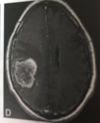

Décrire la photo

IRM cérébrale (T1 avec gadolinium)

Tumeur cérébrale (lésion réhaussée par le produit de contraste)